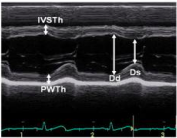

3、HFpEF—左室收缩功能评估

注:LVEDVI (LV end-diastolic volume index) ,左心室舒张末容积指数;

LVESVI ( LV end-systolic volume index),左心室收缩末容积指数.

4、左室收缩功能指标的正常值范围

5、HFpEF—左室舒张功能评估指标

6、多普勒超声指标正常值范围

7、HFpEF—左室舒张功能指标参考值范围